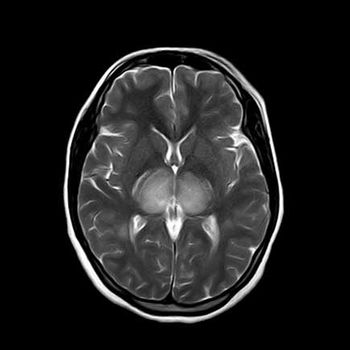

Clinical History: A 45-year-old patient presented with history of irritability, drowsiness, hemiparesis, ataxia and fever for one week. Patient was advised to undergo brain MRI with contrast